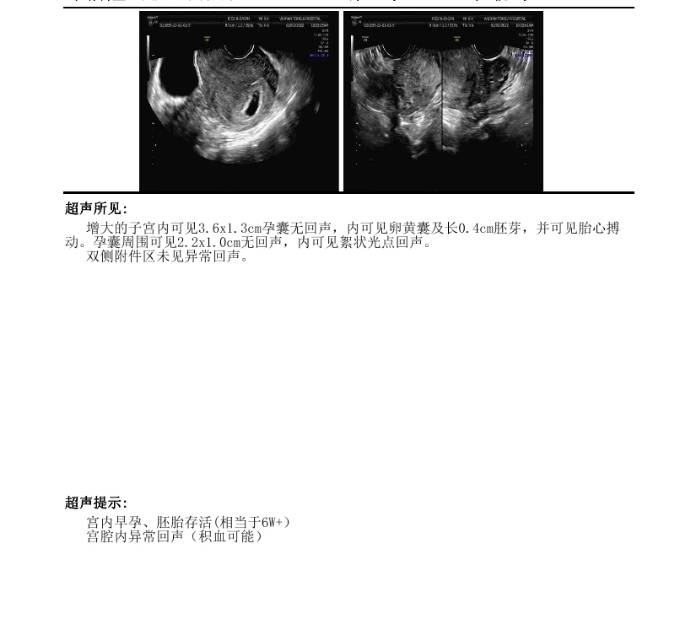

好怕保不住。没有腹痛,有时候也看不到有血,但是b超显示有,要多久才能吸收阿